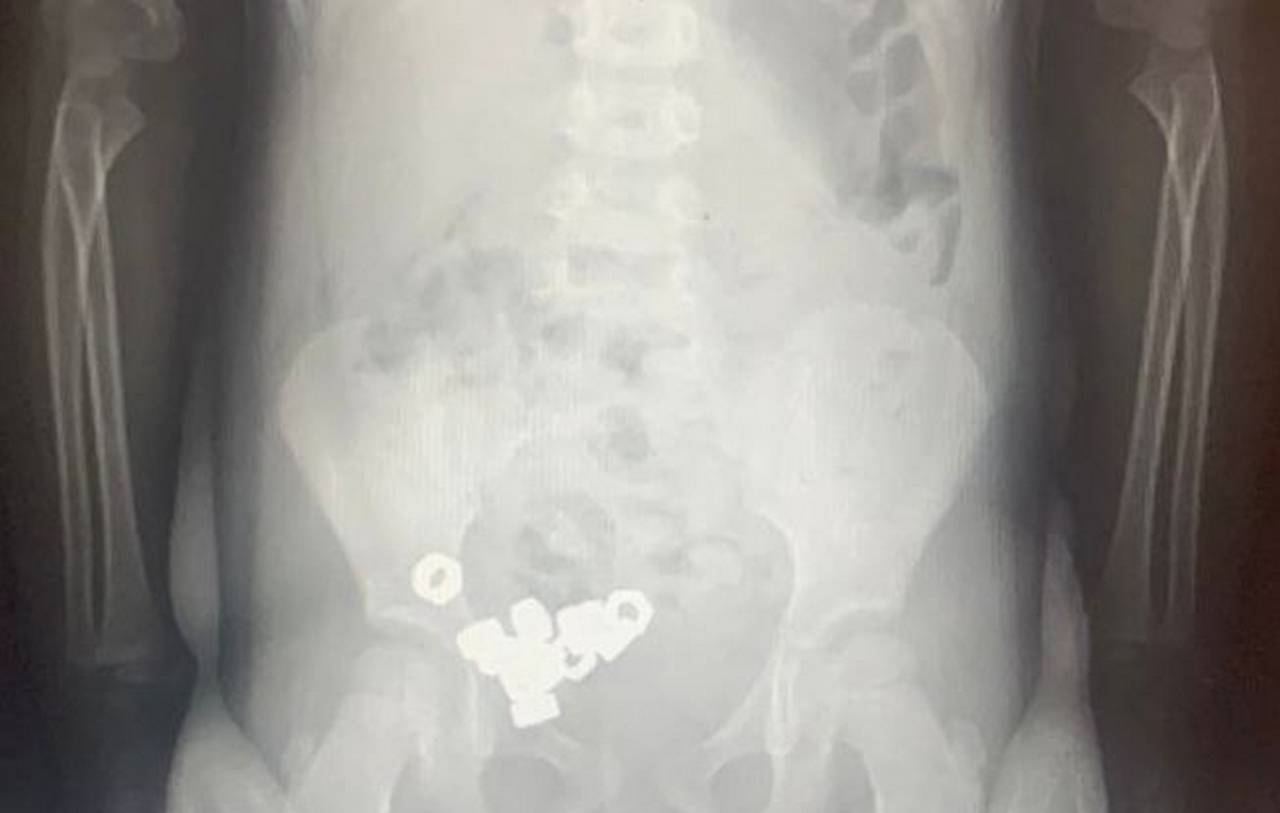

Осмотр не выявил каких-либо специфичных симптомов, однако проведённый рентген органов живота зафиксировал присутствие множества контрастных теней (шестнадцать небольших гаечек) внутри пищеварительного тракта ребёнка, сообщили в региональном Минздраве.

Ребёнок был госпитализирован для постоянного мониторинга состояния ввиду потенциальной угрозы возникновения серьёзных последствий. Поскольку обнаруженные инородные объекты не обладали магнитными свойствами и не представляли собой химически агрессивные вещества, специалисты приняли решение о проведении консервативного лечения: рекомендована специальная диета, постельный режим, наблюдение за характером испражнений и периодическое проведение повторных рентгенологических исследований.